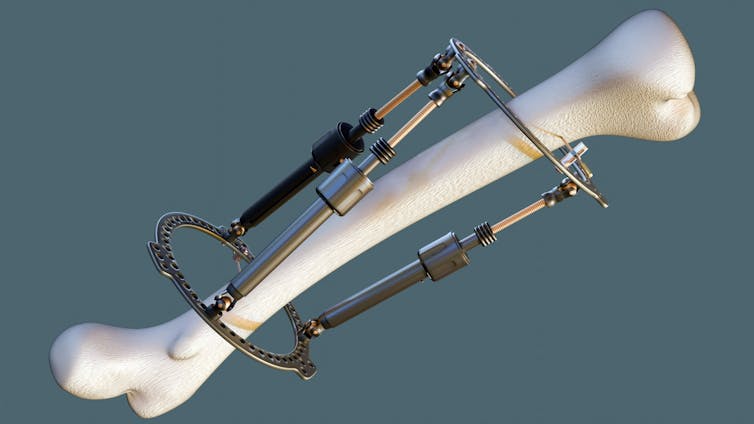

Limb lengthening is not new. The procedure was pioneered in the 1950s by Soviet orthopaedic surgeon Gavriil Ilizarov, who developed a system to treat badly healed fractures and congenital limb deformities. His technique revolutionised reconstructive orthopaedics and remains the foundation of current practice today.

Surgeons begin by cutting through a bone – usually the femur (thigh bone) or tibia (shin bone). To ensure the existing bone stays healthy and that new bone can grow, surgeons are careful to leave intact its blood supply and periosteum (the soft issue that covers the bone).

Traditionally, the cut bone segments were then connected to a bulky external frame which was adjusted daily to pull the two ends apart. But more recently, some procedures have adopted telescopic rods placed inside of the bone itself.

These devices can be lengthened gradually using magnetic controls from outside the body – sparing patients the stigma of an external frame and reducing the risk of infection. However, they’re not suitable for all patients – especially children – and are considerably more expensive than external systems.

Regardless of whether the device sits outside or within the bone, the process is the same. After a short healing period, the device is adjusted to separate the cut ends very gradually, usually by about one millimetre per day. This slow separation encourages the body to fill the gap with new bone – a process called osteogenesis. Meanwhile, the muscles, tendons, blood vessels, skin and nerves stretch to accommodate the change.

Over weeks and months this can add up to a gain of five to eight centimetres in height from a single procedure – the limit most surgeons consider safe. Some patients undergo operations on both the femur and tibia, aiming to gain as much as 12–15 centimetres in total. However, complication rates rise sharply with each centimetre of additional growth. Complications include joint stiffness, nerve irritation, delayed bone healing, infection and chronic pain.